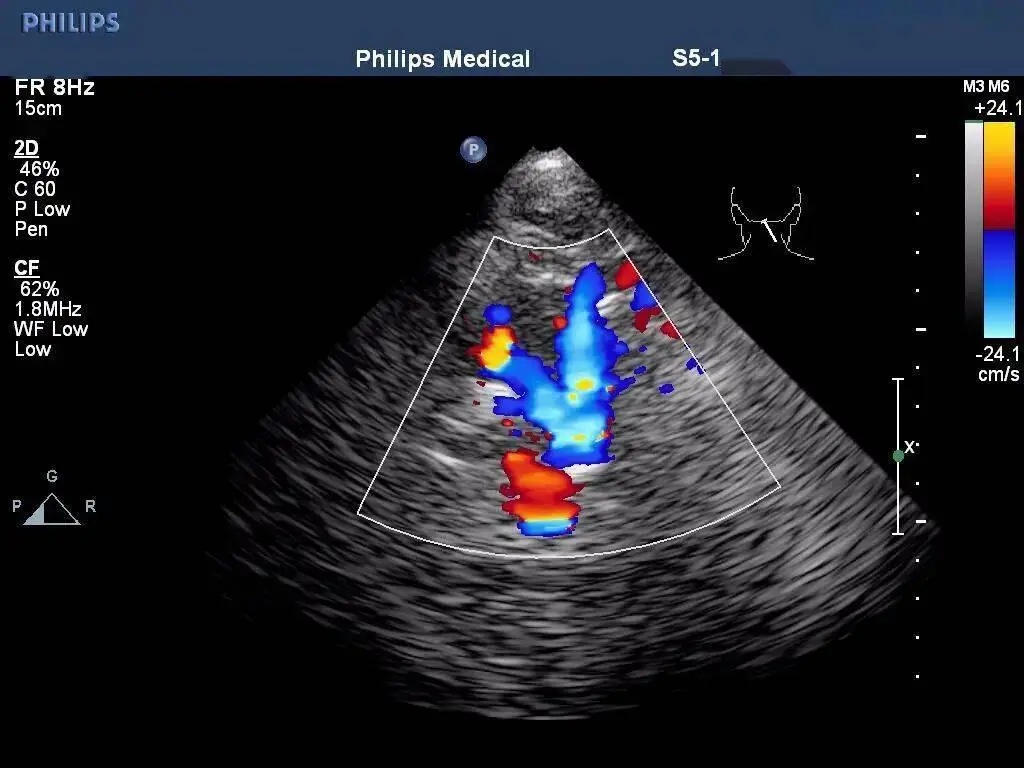

①隐匿型:患侧椎动脉血流频谱显示收缩期"切迹";

②部分型:患侧 VA 血流方向部分逆转,收缩期与舒张期血流方向相反,呈现双向"振荡性"血流频谱;

③完全型:患侧 VA 血流方向完全逆转,呈现单向性血流频谱。

经枕骨大孔平面检查:双侧椎动脉与基底动脉彩色血流成像